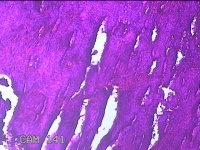

宫颈6点、12点组织

性别

女

年龄

57岁

临床诊断

子宫颈上皮内瘤变[CINⅢ级];子宫颈肿瘤

一般病史

阴道不规则出血1年。

标本名称

大体所见

1.“宫颈6点组织”:灰白粉红色组织1.3x0.8x0.3cm一块。 2.“宫颈12点组织”:灰白粉红色组织1.5x0.7x0.2cm一块。

图3